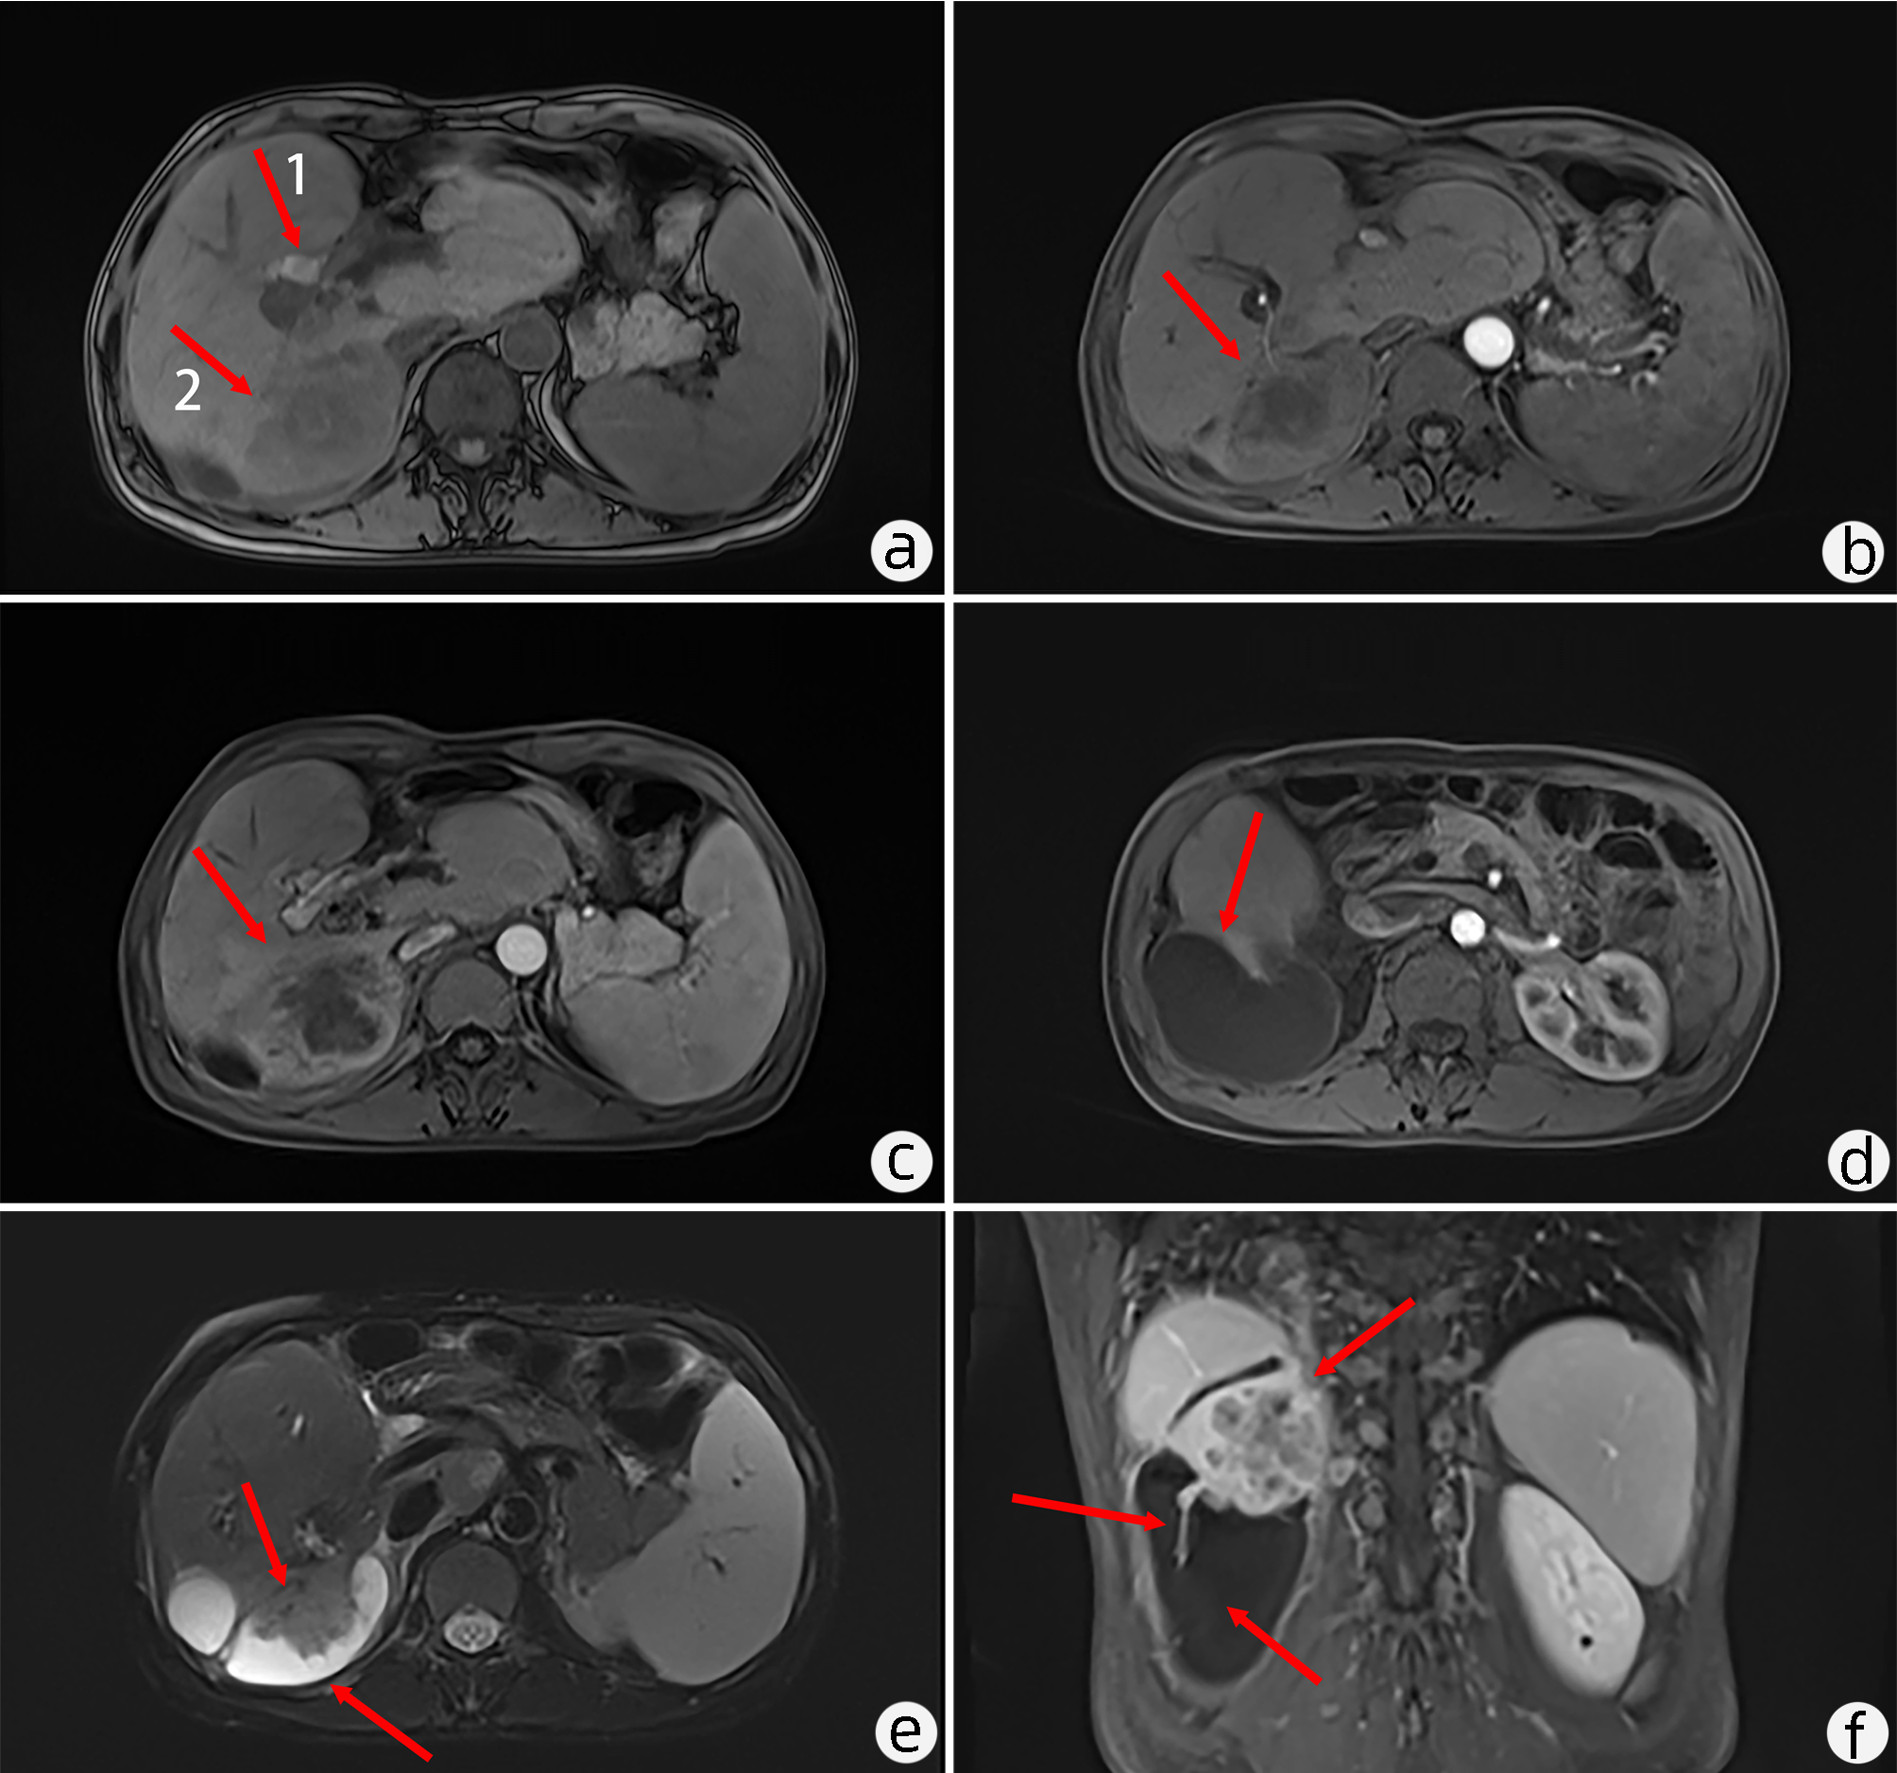

Primary mucoepidermoid carcinoma of the liver: A case report and literature review

Junjie WANG, Cheng CHEN, Yakun WU

2023, 39(1): 152-155. DOI: 10.3969/j.issn.1001-5256.2023.01.023

Abstract(2137) HTML (1487) PDF (3007KB)(131)

Abstract: